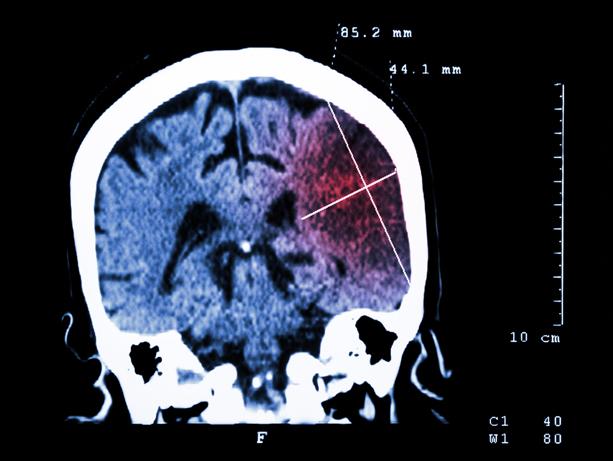

The study identified novel genetic risk factors for any stroke, any ischemic stroke and all major subtypes of ischemic stroke. About 80 percent of strokes are ischemic, which occurs when a blood vessel supplying the brain is blocked.